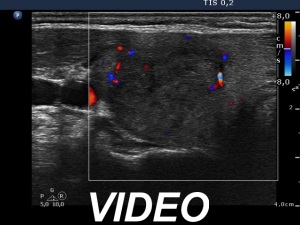

Initial examination (1st and 2nd rows of images):

Ultrasonography: there were multiple hypoechogenic areas with ill-defined borders in both lobes, primarily in the right one. The vascularization was decreased.